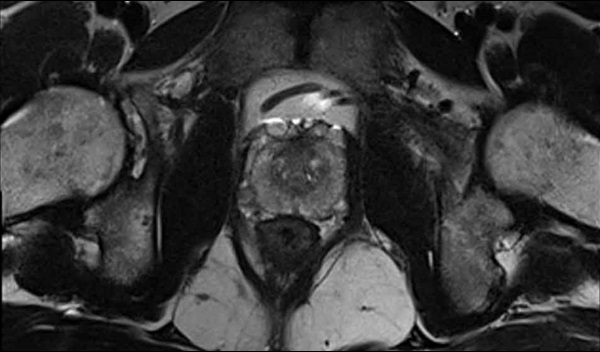

One of the main methods to diagnose prostate cancer is a special type of magnetic resonance Imaging (MRI) scan called a multi-parametric MRI (mpMRI) scan, which helps doctors see if there is any cancer inside the prostate and how quickly the cancer is likely to grow. However, the scan takes 40 minutes and costs £350-450.

The new study looked at the use of a different kind of imaging called multiparametric ultrasound (mpUSS), which uses soundwaves to look at the prostate. The test involves the use of a probe called a transducer to make the images of the prostate. It is placed into the rectum and it sends out sound waves that bounce off organs and other structures. These are then made into pictures of the organs. The doctor doing the test also uses extra special types of ultrasound imaging that look at how stiff the tissue is and how much blood supply tissue has. These are called elastography, doppler and contrast-enhancement with microbubbles. As cancers are more dense and have greater blood supply, they show up more clearly. Although mpUSS is more widely available than mpMRI there has been no large-scale studies to validate its effectiveness as a test to detect prostate cancer cases.